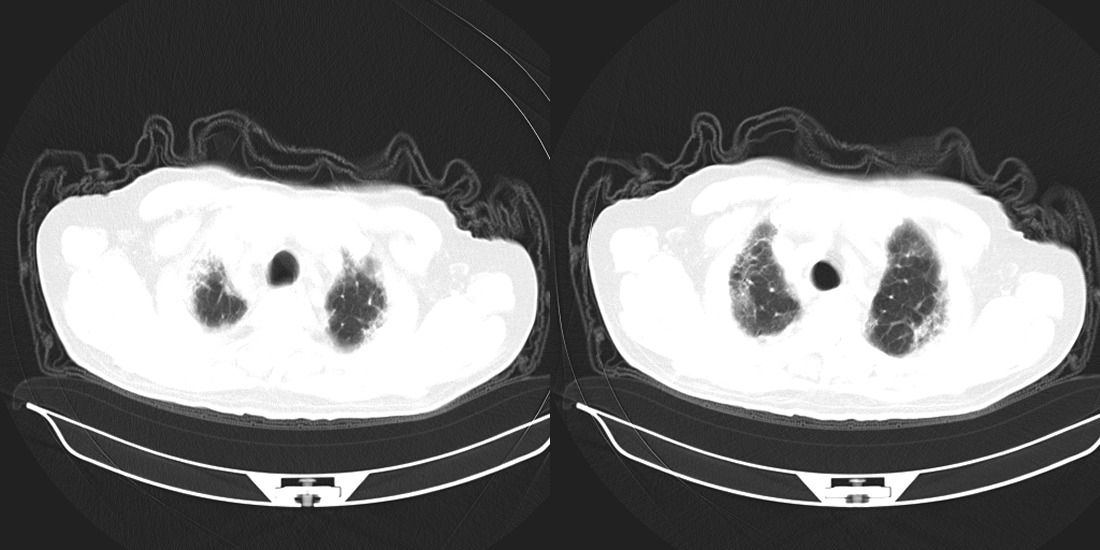

以下是引用zsl6918在2008-2-14 12:15:00的发言:[br]慢支并感染,肺气肿,肺间质纤维化,肺动脉高压。

以下是引用liuyue在2008-2-14 17:25:00的发言:[br]慢支并感染,肺气肿,肺间质纤维化,肺动脉高压 .肺大泡.[br]

以下是引用随光逐影在2008-2-15 11:10:00的发言:[br]1)慢性支气管炎并肺部感染。2)肺间质纤维化。3)肺气肿(多发性肺大泡形成)。4)肺动脉高压。